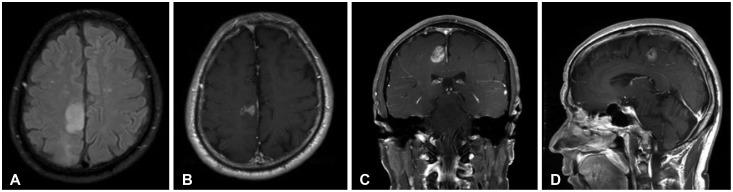

Meningeal dissemination (MDS) of glioblastoma is rare, although its incidence might have been underestimated. MDS of glioblastoma has a fatal course. Thus, rapid and precise diagnosis of MDS is important for further palliative treatment. Unfortunately, MDS of glioblastoma could be diagnosed at a delayed time, causing failure to treat patient optimally. Herein, we present a case of a 56-year-old male with MDS of glioblastoma mimicking chronic subdural hemorrhage (CSDH) after head trauma due to slip down. During treatment for CSDH, MDS of glioblastoma was not controlled appropriately. The patient succumbed to MDS of glioblastoma at 9 weeks after the date of diagnosis of CSDH which could be an MDS.

胶质母细胞瘤的脑膜播散(MDS)较为罕见,尽管其发病率可能被低估了。胶质母细胞瘤的MDS病程凶险。因此,快速准确地诊断MDS对于进一步的姑息治疗很重要。不幸的是,胶质母细胞瘤的MDS可能会被延迟诊断,导致无法对患者进行最佳治疗。在此,我们报告一例56岁男性,其胶质母细胞瘤的MDS表现为滑倒致头部外伤后类似慢性硬膜下血肿(CSDH)。在CSDH治疗期间,胶质母细胞瘤的MDS未得到适当控制。该患者在被诊断为可能是MDS的CSDH后9周死于胶质母细胞瘤的MDS。